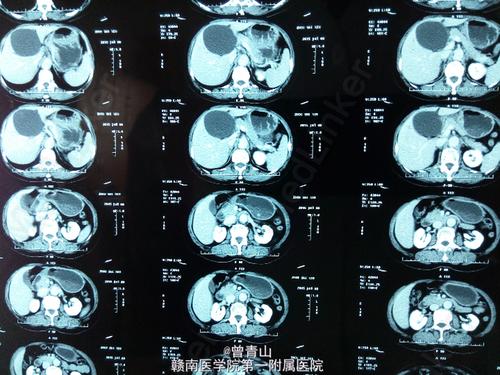

肝囊肿ct图片报告,肝囊肿ct图片

肝囊肿-腹部ct诊断-医学

右肺腺癌多发骨转移伴多发肝囊肿及左肺囊肿一例

肝囊肿一例

肝囊肿ct图片

肝囊肿ct图片影像

肝囊肿ct图片怎么看

多发性肝囊肿ct图片

肝囊肿ct